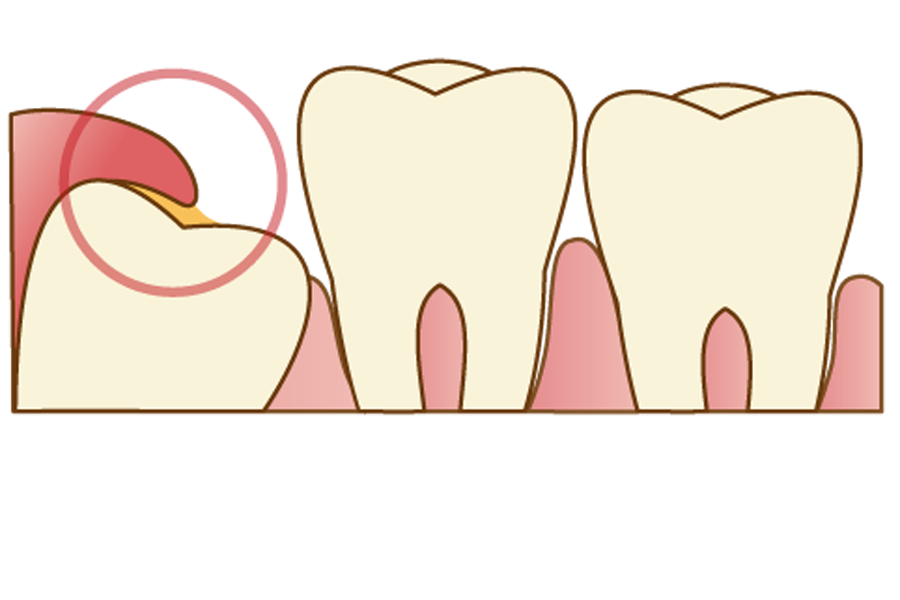

歯茎が上に覆いかぶさっている場合

歯茎が覆いかぶさっている親知らずの場合、歯茎と親知らずの間に汚れがたまりやすく、「智歯周囲炎」を起こしてしまうリスクが高いです。

智歯周囲炎とは、親知らずの周囲に起こる炎症のことで、重症化すると他の人が見てわかるくらいに顔が腫れたり、発熱・倦怠感といった全身症状が起こる場合もあります。

軽度の症状であれば、患部を清潔に保つことで解消されることがほとんどですが、何度も炎症や痛みを繰り返す場合は将来的なリスクを考慮して、早めの抜歯をおススメします。